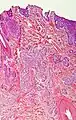

| Cystic basal-cell carcinoma | Morphologically characterized by dome-shaped, blue-gray cystic nodules.[31]: 647 | ![]() | |

| Morpheaform basal-cell carcinoma (also known as "cicatricial basal-cell carcinoma", and "morphoeic basal-cell carcinoma") | Narrow strands and nests of basaloid cells, surrounded by dense sclerotic stroma.[33] | Aggressive[30]: 748 [31]: 647 | ![]() |